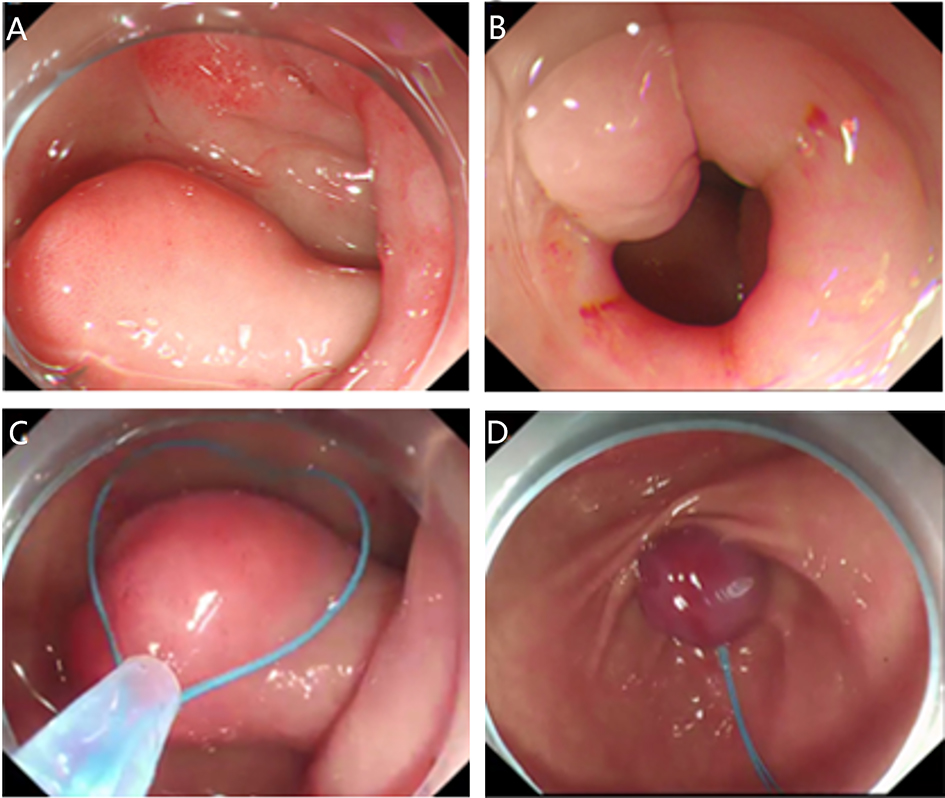

2. Submucosal tunnel endoscopic resection (STER). STER is a new endoscopic technique for the treatment of gastrointestinal muscularis propria tumors; it is an endoscopic surgical modality evolved from POEM, which mainly applies to the excision of gastrointestinal muscularis propria tumors. In sites like the esophagus, gastroesophageal junction, gastric antrum, firstly, one starts by making a small incision in the mucosal surface, then the endoscope goes deeper into it, to create a tunnel in the submucosa, to completely remove the tumor under direct vision, while preserving the integrity of the mucous surface of the digestive tract. After complete resection of the tumor, the opening of the mucosal tunnel was closed with metal clips to avoid perforation of the digestive tract and to reduce postoperative complications such as digestive tract leakage, etc. This method has the advantages of short operation time, less trauma, less pain, low cost, and quick recovery of patients. It can completely dissect the tumor in a single operation, while maintaining the integrity of the digestive tract, and has the same therapeutic effect as classical surgery, and there is no postoperative scar on the surface of the body.